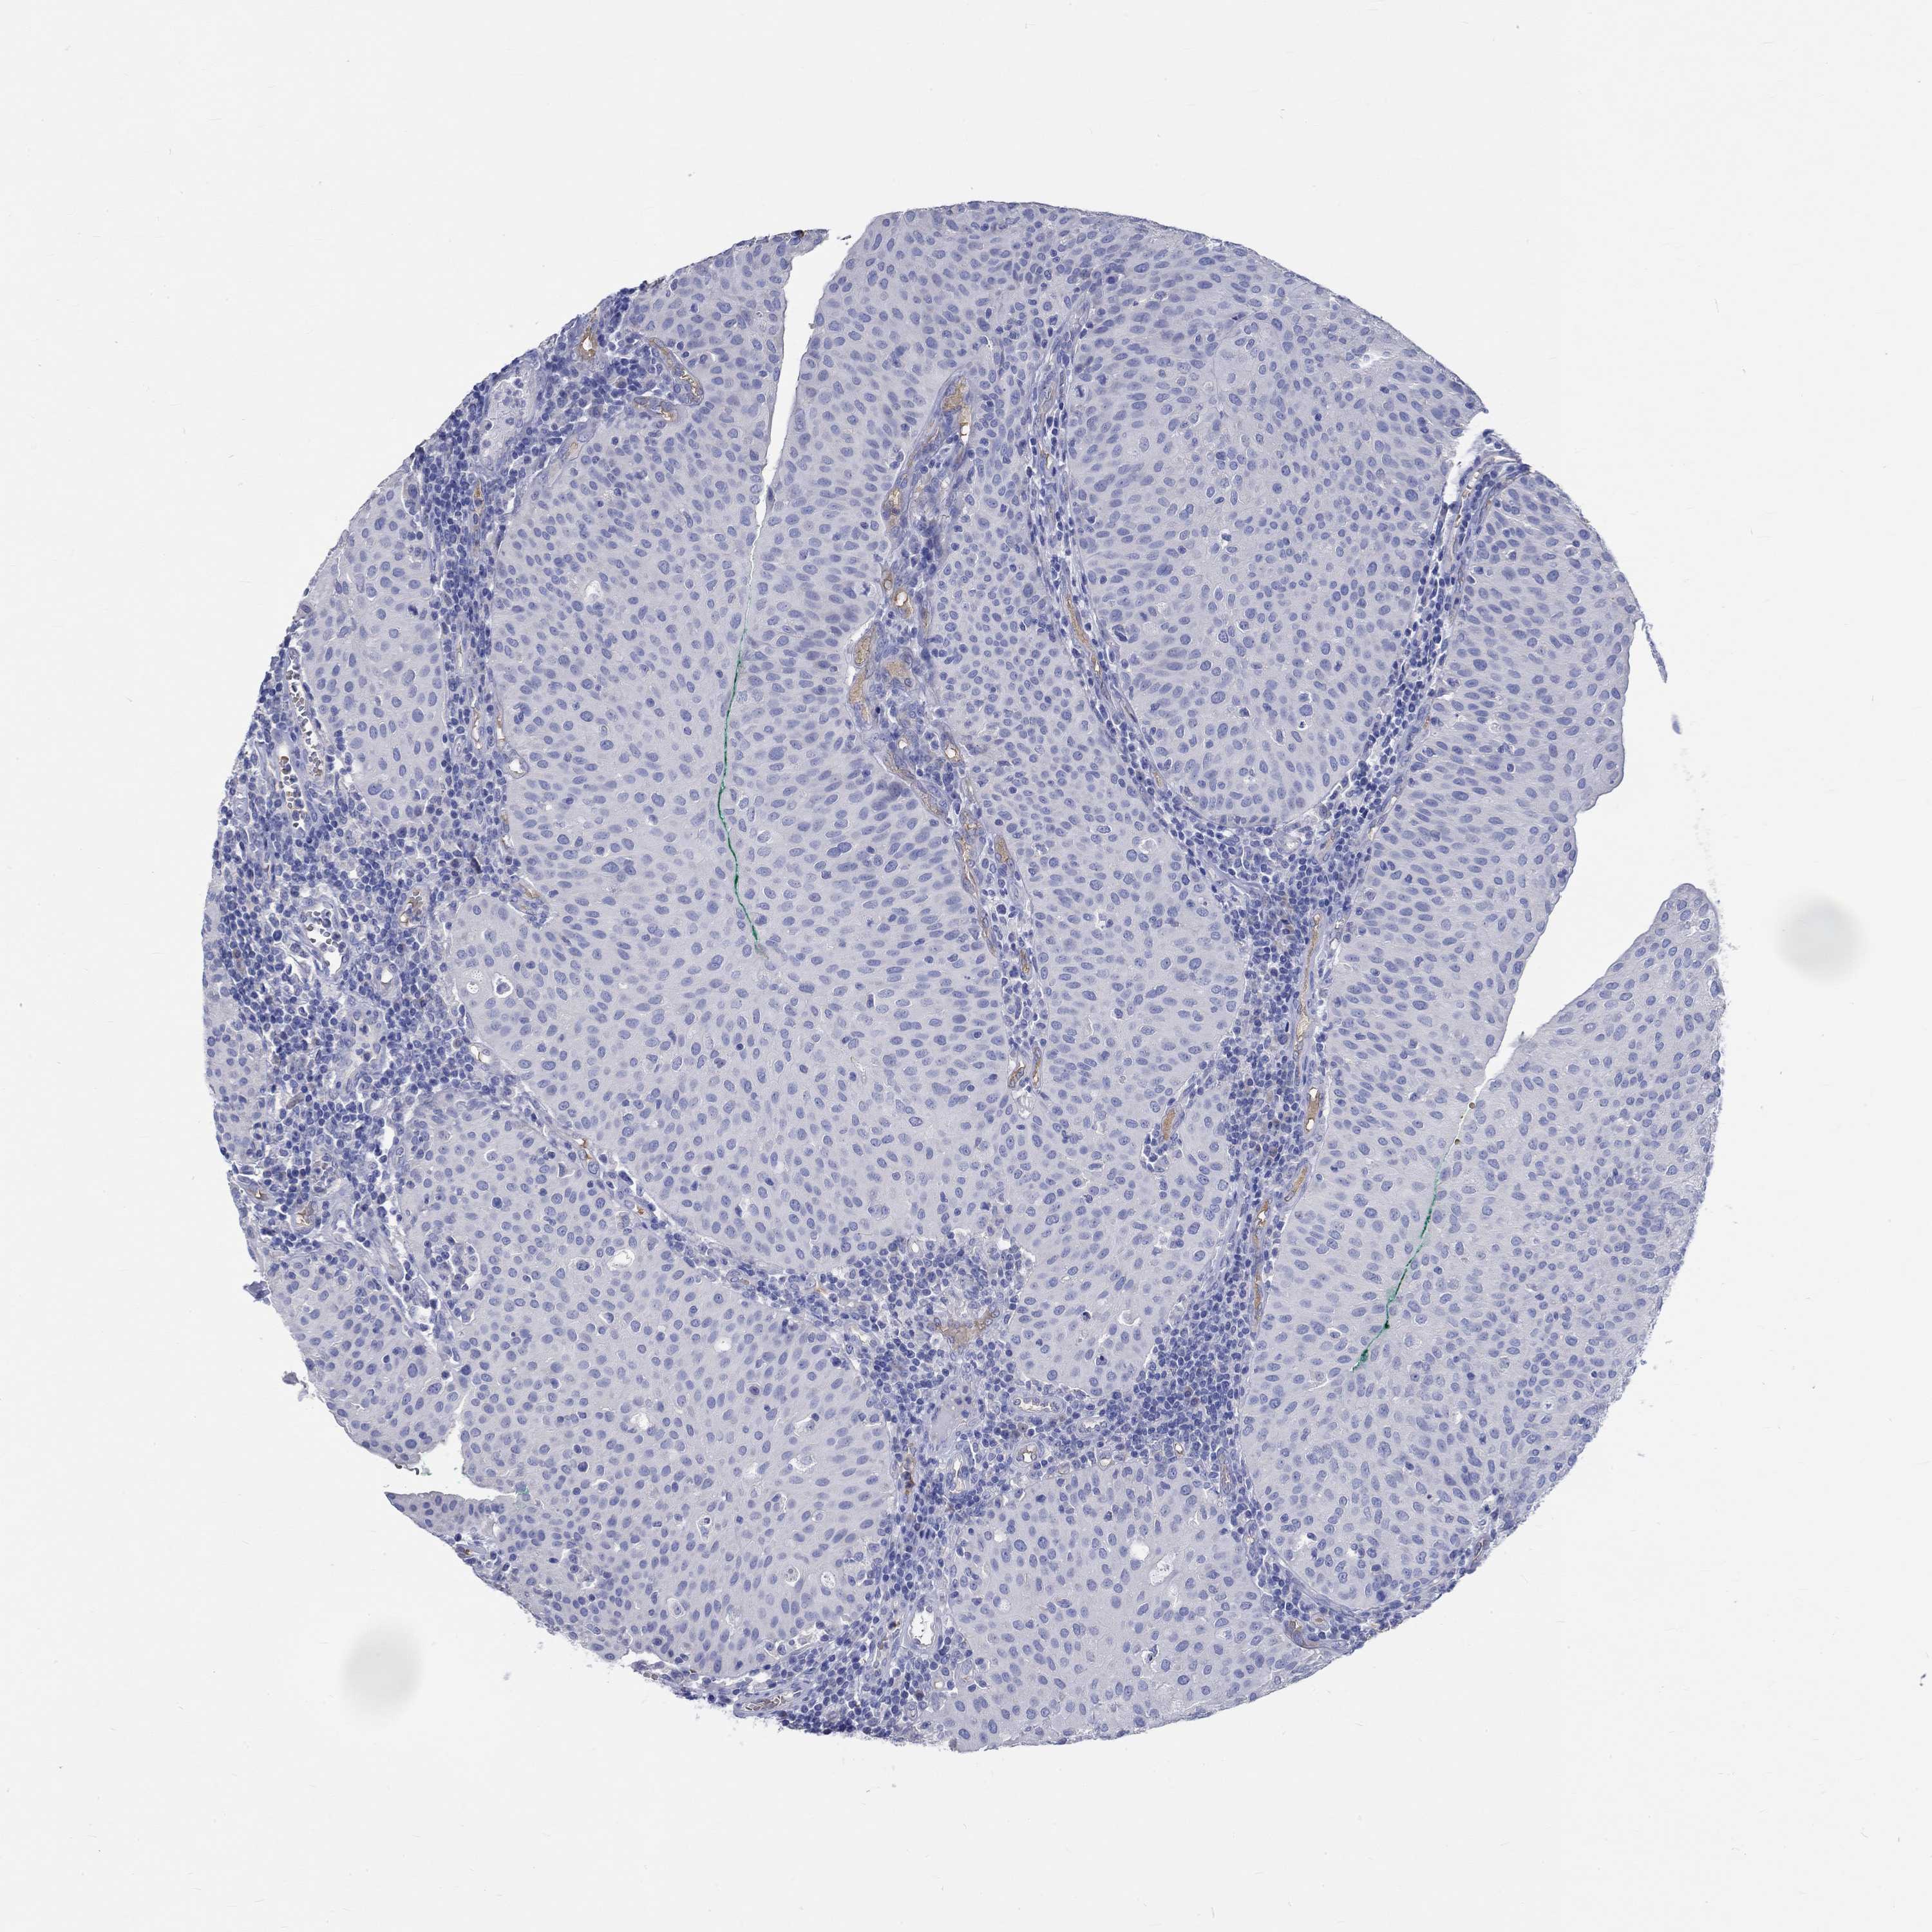

UROTHELIAL CANCER - Protein expressioni

A mouse-over function shows sample information and annotation data. Click on an image to view it in a full screen mode. Samples can be filtered based on level of antibody staining by selecting one or several of the following categories: high, medium, low and not detected. The assay and annotation is described here.

Note that samples used for immunohistochemistry by the Human Protein Atlas do not correspond to samples in the TCGA dataset.

Antibody stainingi

Antibody staining in the annotated cell types in the current human tissue is reported as not detected, low, medium, or high, based on conventional immunohistochemistry profiling in selected tissues. This score is based on the combination of the staining intensity and fraction of stained cells.

Each image is clickable and will lead to virtual microscopy that enables deeper exploration of all samples and also displays staining intensity scores, fraction scores and subcellular localization as well as patient and tissue information for each sample.

Antibody HPA074471

Staining

High

Medium

Low

Not detected

Intensity

Strong

Moderate

Weak

Negative

Quantity

>75%

75%-25%

<25%

None

Location

Nuclear

Cytoplasmic/membranous

Cytoplasmic/membranous,nuclear

Urothelial carcinoma, High grade

Urothelial carcinoma, NOS

Urothelial carcinoma, Low grade